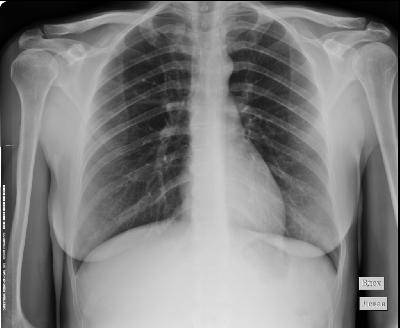

- Деваться было некуда. За быструю сдачу и результаты анализов пришлось заплатить приличную сумму. А когда принесли терапевту заключение, она поморщилась и сразу же отправила нас на рентген, - вздыхая, вспомнил Тагир Оксанович. – Снимок показал затемнение в легких, и поэтому терапевт подтвердила поставленный нам в районной больнице диагноз – пневмония.

При операции оказалось, что случай с пациентом совершенно уникальный. Проблема с легкими – вторичная, а виной ежедневному ухудшению состояния изъян левого желудочка сердца.

- Операция прошла успешно. Хирурги, когда Илдус пришел в сознание после наркоза, сказали, что у него на сердце была опухоль и они ее удалили, но она могла дать метастазы, ему следует наблюдаться в онкологическом диспансере, - продолжал Тагир Оксанович.

Илдус 23 августа 2016 года был выписан с неутешительным диагнозом – саркома левого предсердия третьей стадии.